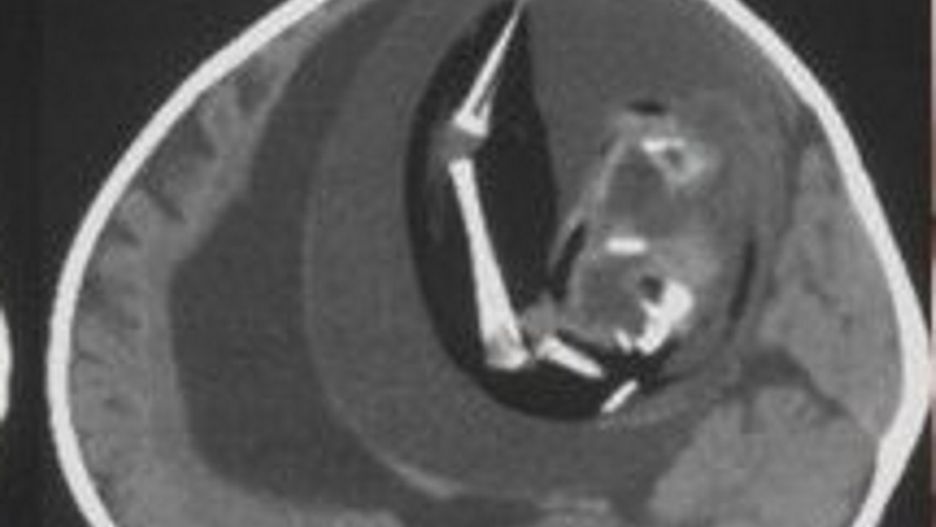

Magazyn naukowy "Neurology" opublikował opis przypadku chińskiej dziewczynki, która miała dość nietypowe objawy: powiększoną głowę oraz problemy z motoryką. Kiedy lekarze z Fudan University w Szanghaju zobaczyli wyniki tomografii komputerowej, od razu zaczęli przygotowywać się do operacji.

W czaszce dziecka znajdowała się dziwna masa, która uciskała mózg i powodowała nagromadzenie się płynu. Dopiero późniejsze badania wykazały, że był to jej… bliźniak. Płód został wchłonięty na wczesnym etapie ciąży przez silniejszego bliźniaka.

"Proszę zwrócić uwagę na ten skan. Widać wyraźnie wodogłowie, ściśnięty mózg, a także płód z kręgosłupem, kością udową i piszczelem. Masa płodowa ma kończynę górną i palce" – napisał na Twitterze Oren Gottfried, neurochirug.